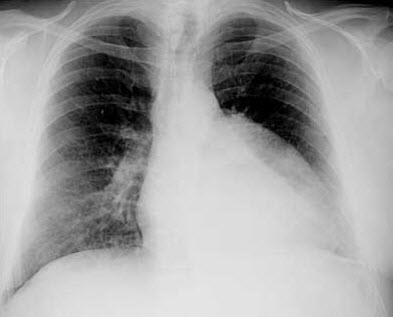

Chest films are ordered.

Chest radiographymay reveal such diagnostic features as:

- LV hypertrophy.

- The classic sign of rib notching, which is caused by erosion of the lower edges of the ribs by dilated intercostal arteries.

- The "reverse 3" sign related to the aortic arch and descending aorta. The upper part of the 3 is formed by the dilated proximal segment descending into the coarctated segment. The bottom portion of the 3 is formed by the coarctated segment as it exits into the normal distal segment of the aorta.